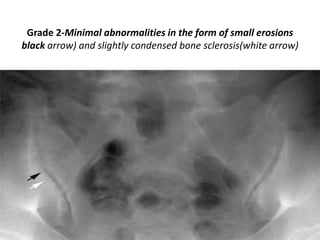

Grades of Sacroiliitis- according to

the New York criteria

Grade 0-

Grade 1-Suspicious changes at the left sacroiliac joint in the

form of slightly irregular joint facets.

Grade 2-Minimal abnormalities in the form of small erosions

black arrow) and slightly condensed bone sclerosis(white arrow)

Grade 3-Manifest abnormalities in the form of erosion and

sclerosis

in addition to widening of the middle part of both sacroiliac

joints.

Grade 4-Total ankylosis of both sacroiliac

joints

.